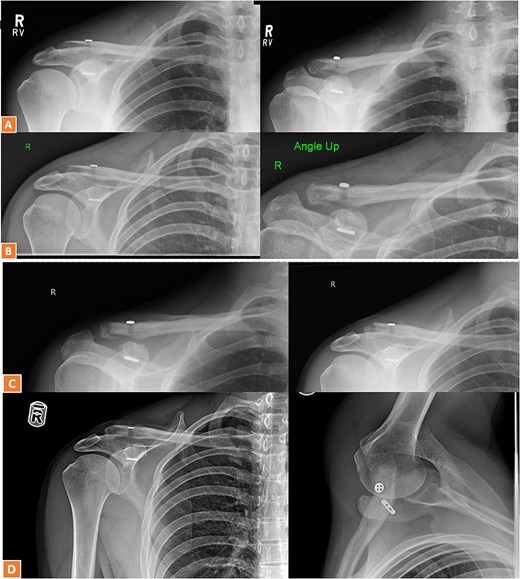

A 27-year-old male suffered a right lateral clavicle fracture after a fall (Fig. 5). He underwent TightRope fixation with stabilization of the coracoclavicular ligament. Rehabilitation was initiated early, and by three months, he had full shoulder motion and returned to overhead sports. Radiographs confirmed union, and the patient reported minor scar sensitivity and transient keloid formation, with no functional limitations (Fig. 6A–D).

(A, B) Radiographs showing healing of the third case and radiological union at 6 weeks and 3 months post-operatively. (C–D) Radiographs showing complete healing of the third case and union at 6 months and 12 months post-operatively.